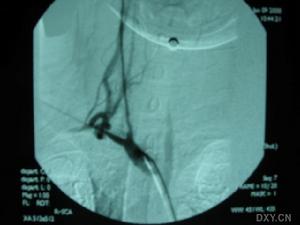

4.血管造影

對頭臂血管、胸-腹主動脈、腎動脈、肺動脈進行全面檢查。明確狹窄部位、程度、側支情況等。冠狀動脈造影明確冠狀動脈狹窄的部位、程度。